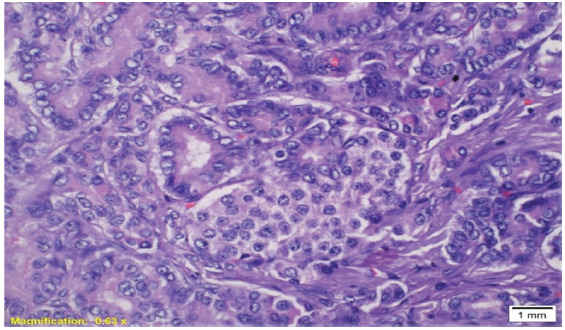

We report a rare and intricate case of nesidioblastosis, marked by hyperinsulinemic hypoglycemia, in a patient with diabetes and chronic kidney disease (CKD). PET-CT imaging and histopathology confirmed the condition, culminating in a comprehensive treatment strategy comprising subtotal pancreatectomy and pharmacotherapy. This case marks the first documented occurrence of nesidioblastosis in a patient with CKD and diabetes. The presence of CKD further complicated the clinical picture, influencing hypoglycemic risk, drug efficacy, insulin clearance, and counter-regulatory mechanisms.